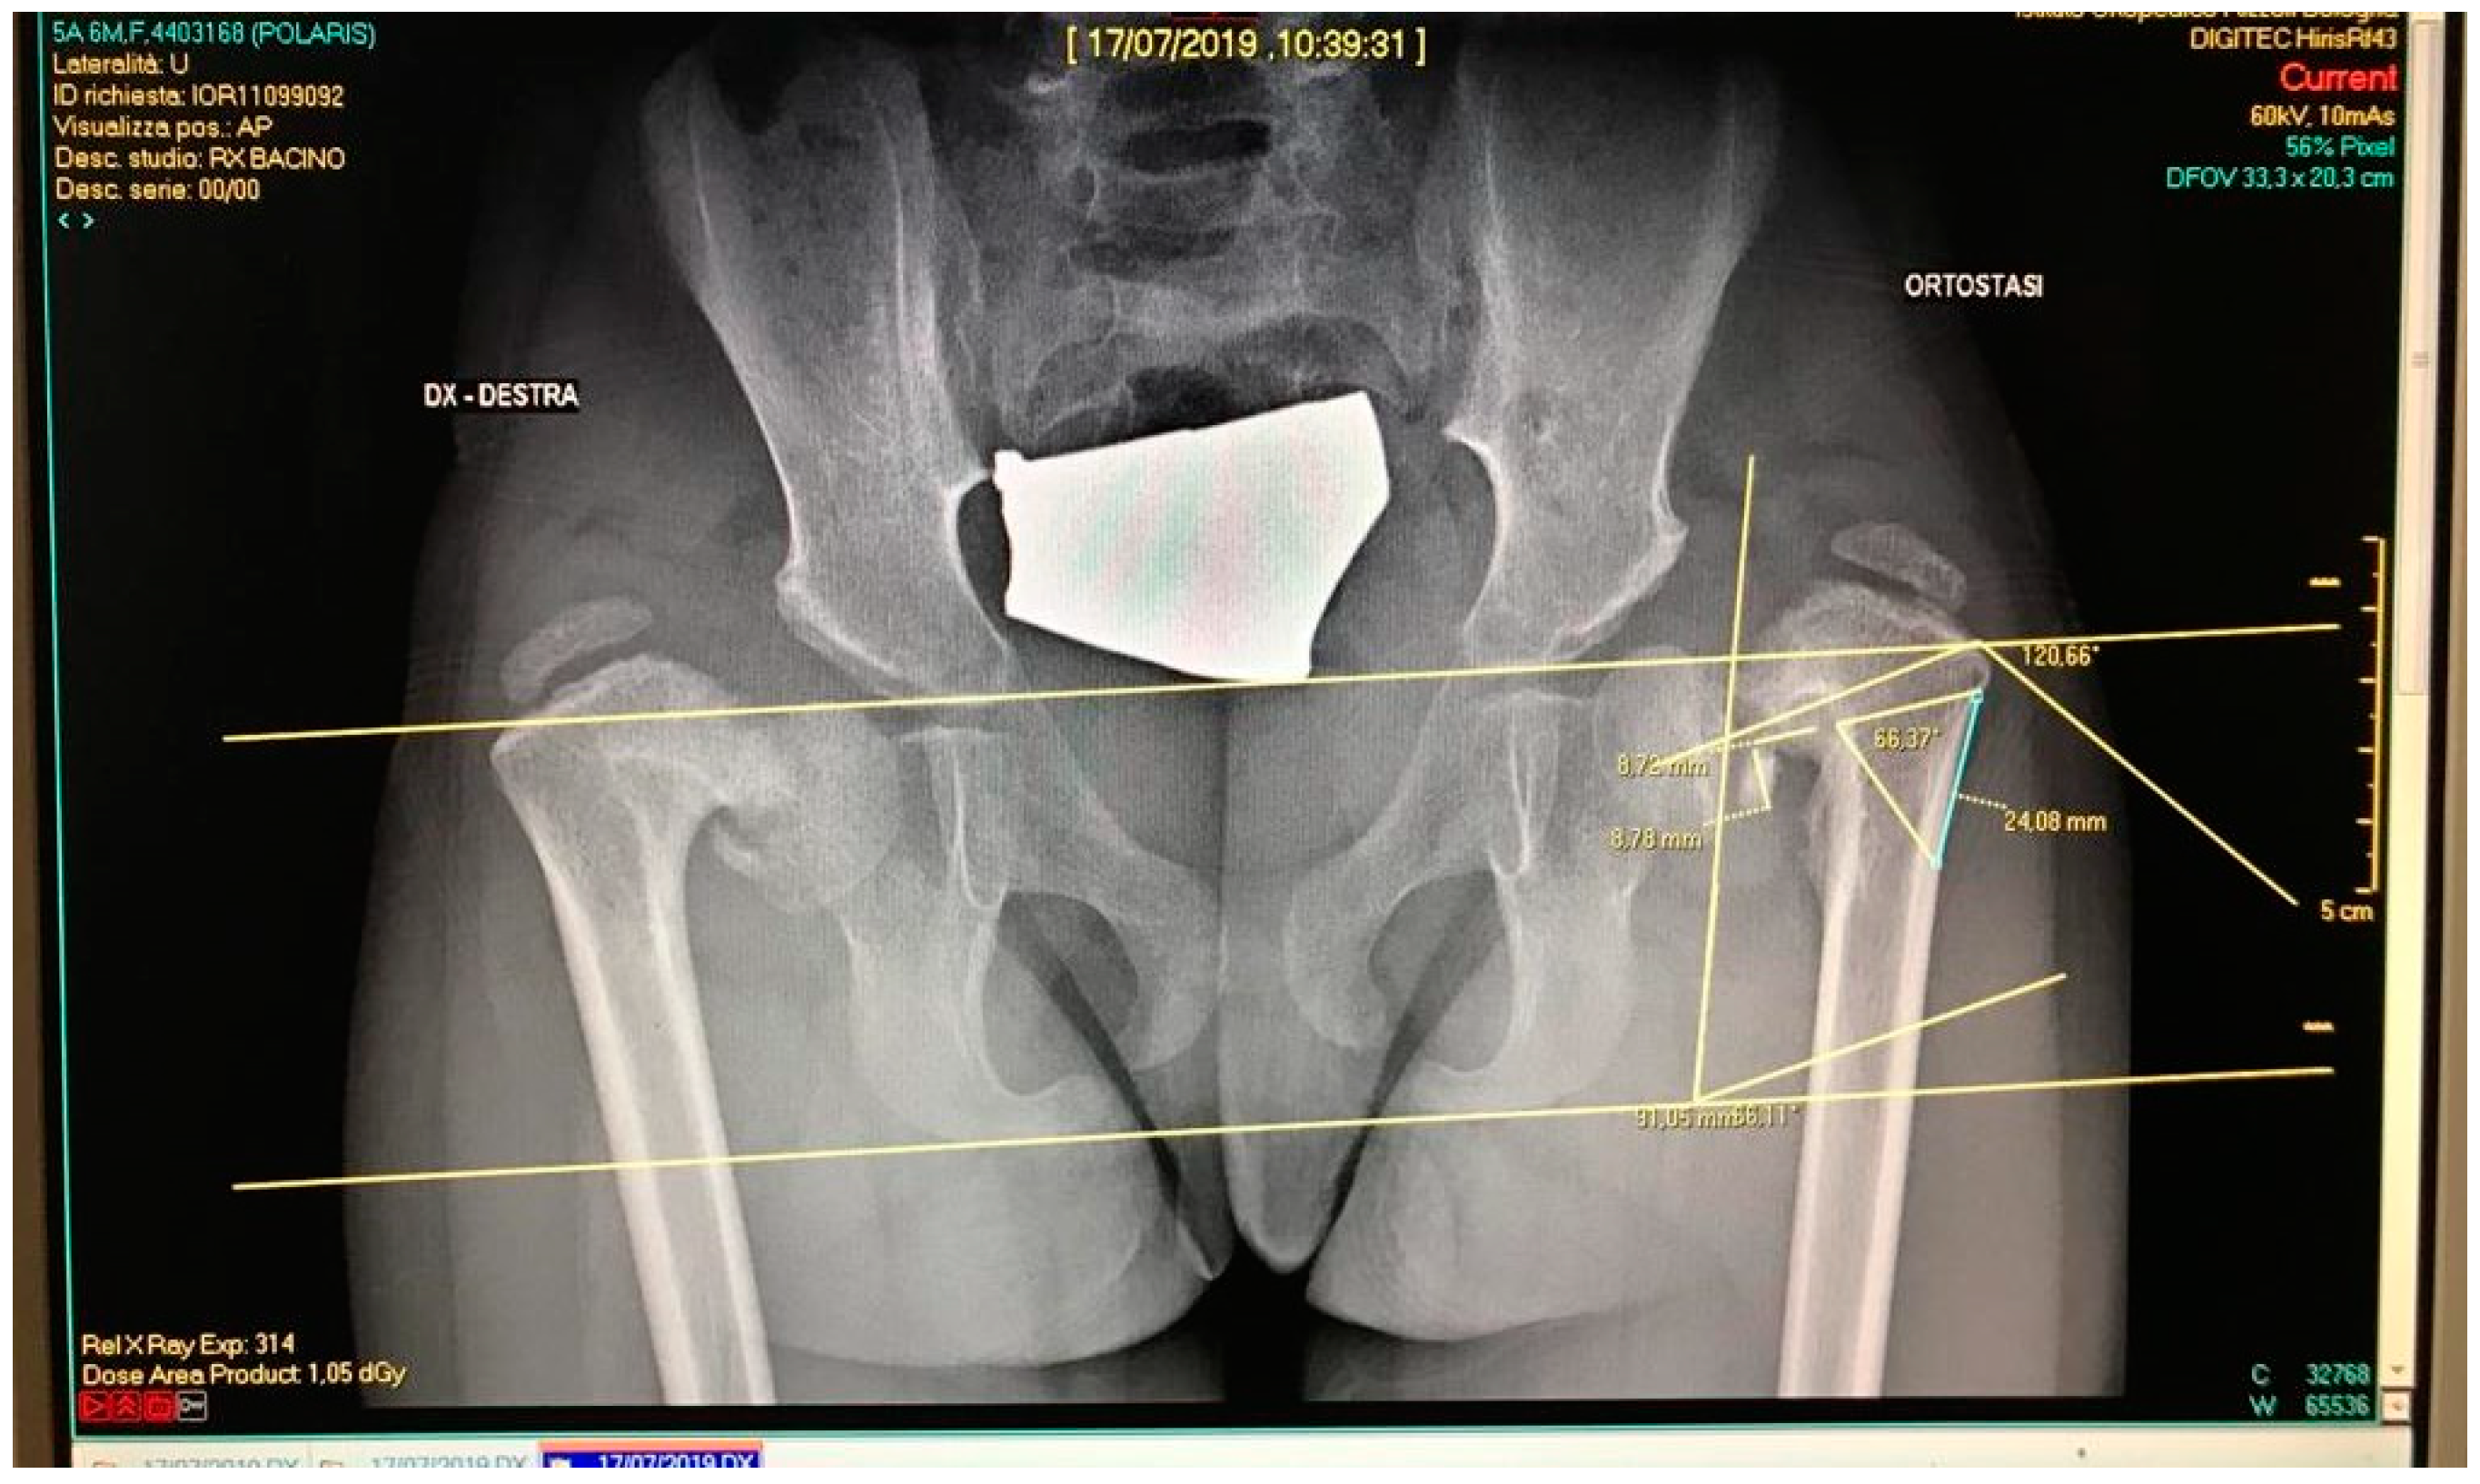

2.1. Case Study

2.2. CAM and CAD-CAT

2.3. CASS and CCG Design